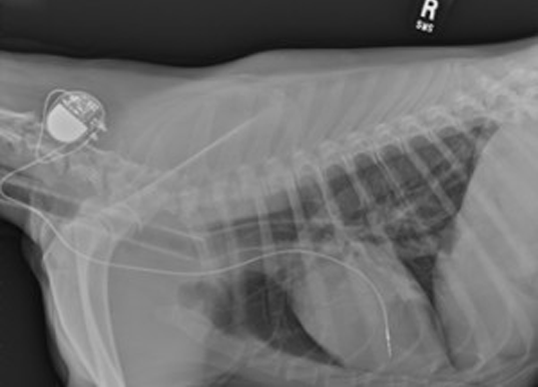

일반 X-Ray 촬영검사

흉부, 복부, 두부, 근골격계, 척추 촬영을 통해 환자 전반에 걸친 기본적인 정보를 획득할 수 있는 손쉬운 진단방법입니다. 본원 영상의학과의 X-선 검사장비는 디지털 검사장비를 도입하여 영상의 구현과 검사시간을 단축하였으며, 촬영시간은 물론 촬영 대기시간, 촬영에서 진단까지의 시간이 단축되어 환자 서비스 향상을 이룰 수 있습니다. 만일 촬영 후에 사진이 만족스럽지 않은 경우라 하더라도 촬영 후에 농도조정이 가능하기 때문에 불필요한 재촬영을 대폭 줄일 수 있습니다.